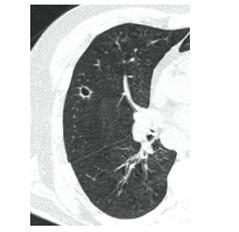

КТ имеет высокую чувствительность в выявлении изменений в легких, характерных для COVID-19. Применение КТ целесообразно для первичной оценки состояния ОГК у пациентов с тяжелыми прогрессирующими формами заболевания, а также для дифференциальной диагностики выявленных изменений и оценки динамики процесса. КТ позволяет выявить характерные изменения в легких у пациентов с COVID-19 еще до появления положительных лабораторных тестов на инфекцию с помощью МАНК. В то же время, КТ выявляет изменения легких у значительного числа пациентов с бессимптомной и легкой формами заболевания, которым не требуется госпитализация. Результаты КТ в этих случаях не влияют на тактику лечения и прогноз заболевания при наличии лабораторного подтверждения COVID-19. Поэтому массовое применение КТ для скрининга асимптомных и легких форм болезни не рекомендуется.

4. Все выявляемые при лучевых исследованиях признаки, включая КТ-симптомы, не являются специфичными для какого-либо вида инфекции и не позволяют установить этиологический диагноз. Вне клинической (эпидемической) ситуации они не позволяют отнести выявленные изменения к пневмонии COVID-19 и дифференцировать их с другими пневмониями и невоспалительными заболеваниями. Данные лучевого исследования не заменяют результаты обследования на РНК SARS-CoV-2. Отсутствие изменений при КТ не исключают наличие COVID-19 и возможность развития пневмонии после проведения исследования.